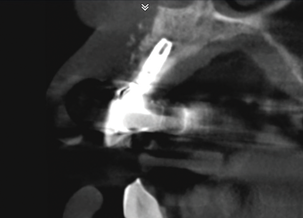

(2.) Preoperative CBCT analysis demonstrating a fistula from the site of the radiolucency to the oral environment.

Figure 2

In this case, a dental implant that had been placed 10 years prior was functional, stable, and esthetically acceptable to the patient. However, a significant fistula was present on the facial-apical aspect of the ridge in the maxillary lateral incisor area. This area was painfully sensitive to touch and demonstrated purulence when squeezed. To evaluate the lesion, first, a conventional digital radiograph was acquired, which revealed an apical radiolucency at the apex of the implant (Figure 1). Further analysis using cone-beam computed tomography (CBCT) demonstrated a fistula from that site to the oral environment (Figure 2). Treatment options were discussed, including removal of the implant, followed by grafting, a healing period, and replacement of the implant and implant-retained crown. If this option was selected, a transitional appliance would need to be created. Another option was to attempt to salvage the implant and implant crown by treating the infection and grafting the site to create a new boney wall and eliminate the fistula. Ultimately, the patient accepted this option to attempt to salvage the fixture and crown.

Peri-implantitis was not the culprit behind the creation of this infected site; the lesion developed as a result of the position of the implant. Although the implant was initially stable upon placement, it was angled such that its apex had penetrated through the facial plate of bone. Without a sagittal CBCT analysis or a releasing flap performed to evaluate the initial placement, the surgeon could easily miss this. Regardless, the circumstances warranted evaluation of the apical aspect of the implant to attempt to salvage it.

(14.) Follow-up 8-week postoperative CBCT analysis of the area demonstrating closure of the diseased site, absence of the radiopaque lesion, and new facial wall formation.

Figure 14